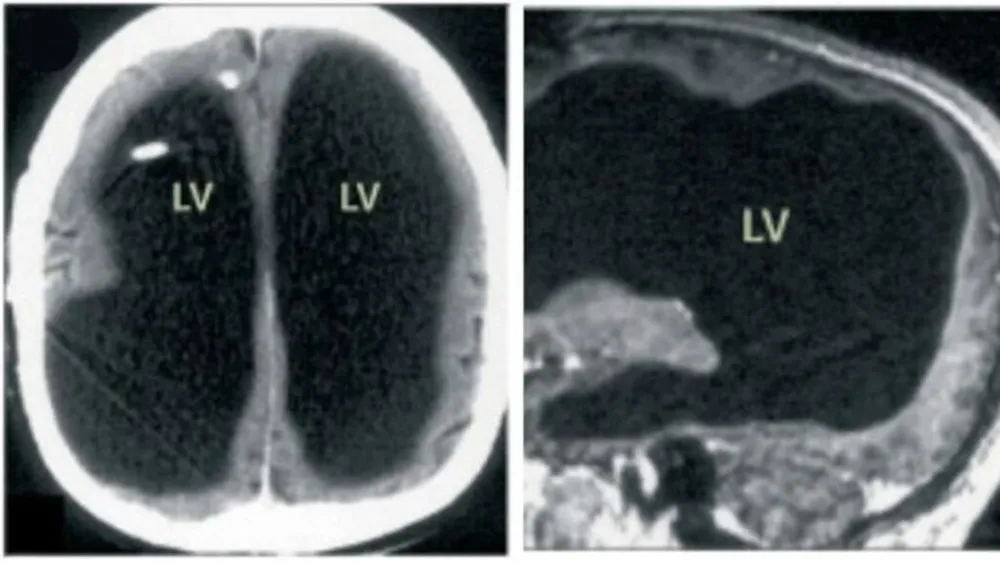

Fransa’nın güneyinde yaşayan bir adam, hafif bacak ağrısı şikayetiyle doktora başvurduktan sonra inanılmaz bir gerçekle yüzleşti. Yapılan taramalarda, yıllarca yarım beyin ile yaşadığını öğrendi.

Adam, beyninin yarısından fazlasının olmadığını öğrendi.

Beyin taraması sonrası adamın beyninin yarısının olmadığı, "Hidrosefali" adı verilen kafatasında ince bir beyin dokusu tabakası ve sıvı bulunduğu ortaya çıktı.

Doktorlar, hastalığının nedeninin beyninde biriken sıvı olduğunu ve bu durumun 30 yıl boyunca beyninin büyük kısmının tahrip olmasına yol açtığını düşünüyor.

Öte yandan hastalık bebekken teşhis edilmiş ve stent takılmıştı. Ancak 14 yaşındayken stent çıkarıldığında, beyninin büyük bir kısmı aşınmaya başladı.

Geçmişte, bilincin belirli beyin bölgeleriyle bağlantılı olduğu düşünülüyordu; ancak bu tür hikayeler, bilincin yalnızca belirli bir bölge tarafından yönetilmediği fikrini savunan yeni teorilerin ortaya çıkmasına neden oldu.